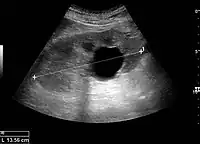

Renal cyst as seen on abdominal ultrasound